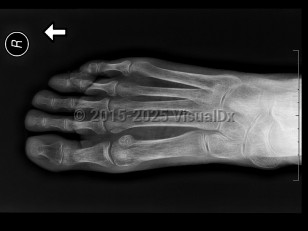

GoutGout

Psoriatic arthritisPsoriatic arthritis